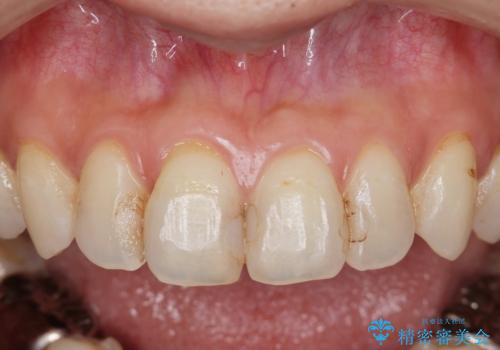

前歯の劣化したコンポジットレジン修復をセラミッククラウンへ

- 数年前に前歯の虫歯治療し、コンポジットレジン修復がなされてい箇所の審美障害の改善を希望され来院されました。

再度レジン修復を行うか、劣化のスピードは遅いが歯の削合が必要なセラミッククラウンの治療の選択肢をご提案し、今後のやりかえの心配の少ないセラミッククラウン治療を希望されました。